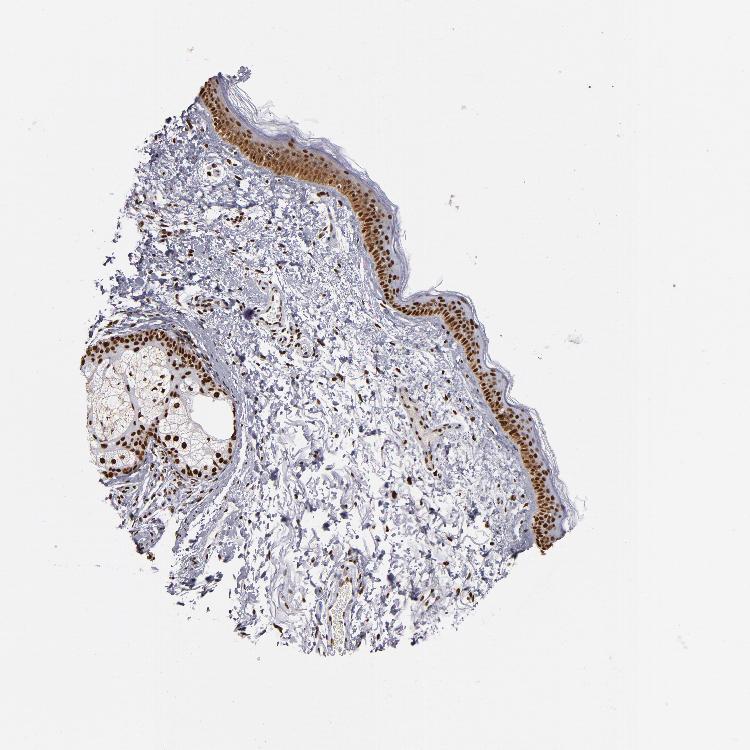

SKIN 1 - Antibody stainingi

Antibody staining in the annotated cell types in the current human tissue is reported as not detected, low, medium, or high, based on conventional immunohistochemistry profiling in selected tissues. This score is based on the combination of the staining intensity and fraction of stained cells.

Each image is clickable and will lead to virtual microscopy that enables deeper exploration of all samples and also displays staining intensity scores, fraction scores and subcellular localization as well as patient and tissue information for each sample.

Antibody HPA002691Antibody CAB004081

Langerhans HighMedium

Fibroblasts HighHigh

Keratinocytes HighMedium

Melanocytes HighMedium

SKIN 2 - Antibody stainingi

Epidermal cells HighMedium